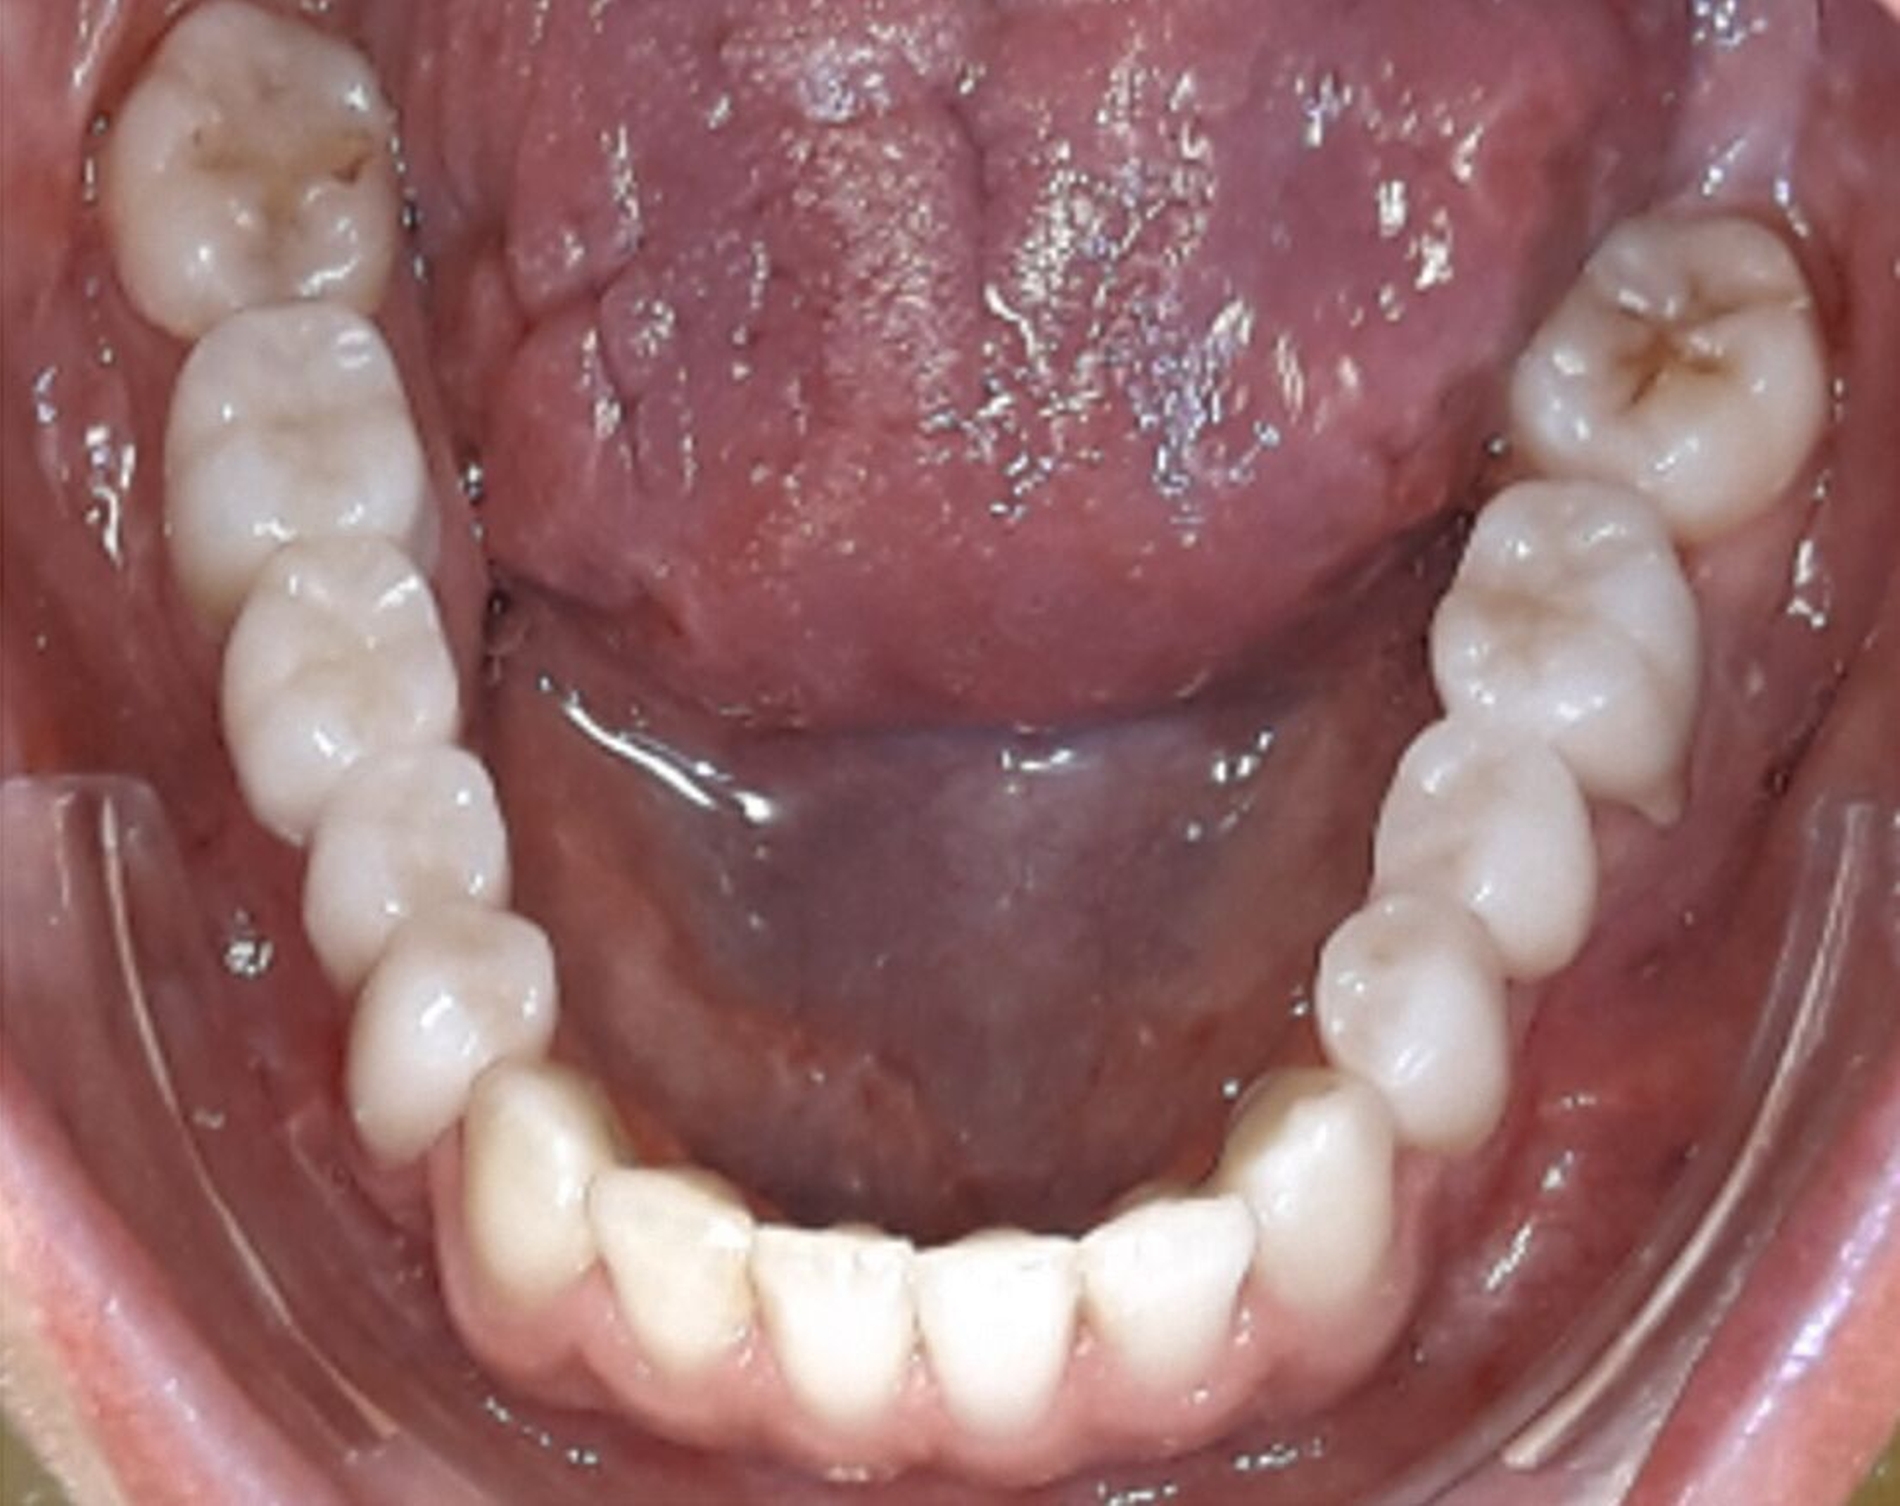

Aufgrund einer hohen Kariesanfälligkeit und einer klinisch floriden Parodontitis waren bereits mehrere Zähne des Patienten extrahiert worden, darunter 16, 11, 25, 38, 35, 45 und 46. Die mesiale Kippung und Aufwanderung der angrenzenden Zähne ließ vermuten, dass der Zahnverlust zeitlich weiter zurücklag. Aufgrund der reduzierten Langzeitprognose des Zahnes 11 entschieden wir uns gemeinsam mit dem Patienten für eine Ausgleichsextraktion des Frontzahns.

Außerdem wurde vor der kieferorthopädischen Intervention die Parodontitis vom Hauszahnarzt behandelt, so dass im Anschluss eine Multiband-Apparatur im Ober- und im Unterkiefer eingesetzt und die Zahnbögen nivelliert werden konnten. Dabei wurden die seitlichen Schneidezähne 12 und 22 anstelle der Zähne 11 und 21 lückig eingeordnet. Die Lücken in Regio 35 und 45 wurden für eine spätere Versorgung vorbereitet.